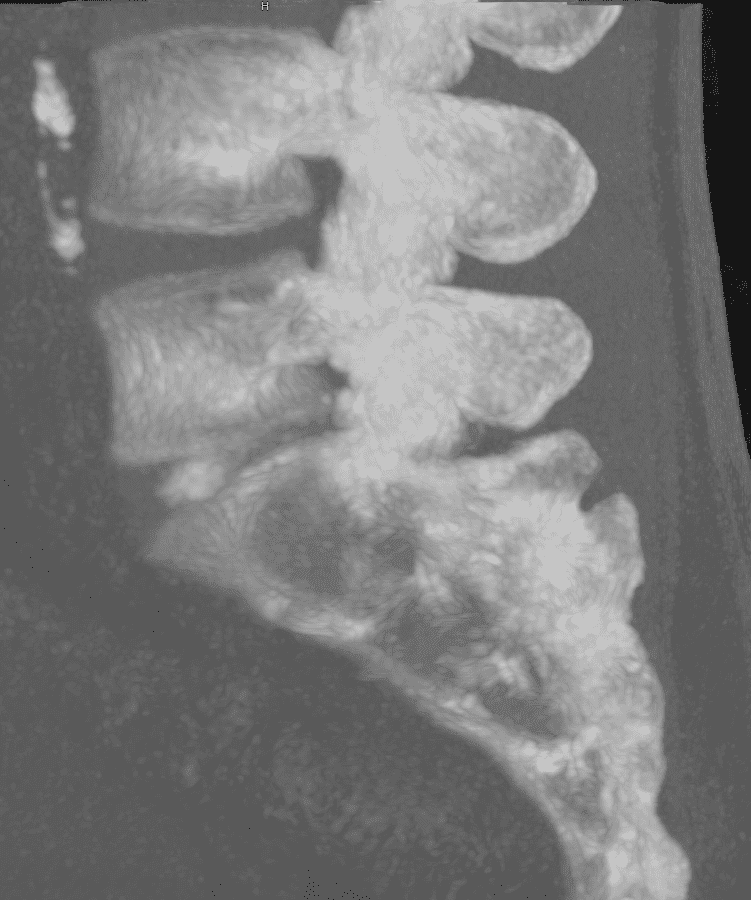

La technique repose sur la compréhension de la physiopathologie de la hernie discale. Dans le cadre d’une hernie contenue, l’extrusion modérée du noyau pulpeux entraîne une augmentation de la pression interne du disque, qui se traduit par une compression des racines nerveuses. La nucléotomie percutanée permet de diminuer cette pression en retirant une fraction du noyau, ce qui contribue à la réduction de la hernie et à l’amélioration des symptômes cliniques.

Résection du noyau pulpeux

Une fois l’aiguille en place, des instruments spécialisés (curettes ou dispositifs aspiratifs) sont utilisés pour retirer une portion du noyau pulpeux.

Cette résection permet de diminuer la pression interne, facilitant le repositionnement du disque et la réduction de la hernie.